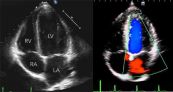

Tiến hành thăm dò mặt cắt từ mỏm được nhận xét là sẽ khó hơn nhưng kỹ thuật này có tác dụng trong so sánh kích thước buồng thất và là cửa sổ tốt nhất nhằm đánh giá những bất thường về vận động ở vùng vách liên thất và thành tim. Dưới đây là hình ảnh mặt cắt siêu âm quét 4 buồng từ mỏm tim trong siêu âm tim bẩm sinh. Mời các bạn tham khảo!

Thăm dò vị trí mặt cắt cạnh ức trục ngắn giúp thu được hình ảnh bằng cách xoay đầu dò một góc 90 độ thuận chiều kim đồng hồ, sau đó quét đầu dò từ đáy tim lên đến mỏm tim để thu được các mặt cắt ngang khác nhau. Dưới đây là hình ảnh về mặt cắt quét dưới mũi ức trục ngắn trong siêu âm tim bẩm sinh. Mời các bạn tham khảo!

Siêu âm tim là phương pháp chẩn đoán hình ảnh không xâm lấn, an toàn và được sử dụng rất phổ biến trong xác định những bất thường của tim. Dưới đây là hình ảnh về mặt cắt quét dưới mũi ức trục dài trong siêu âm tim. Mời các bạn tham khảo!